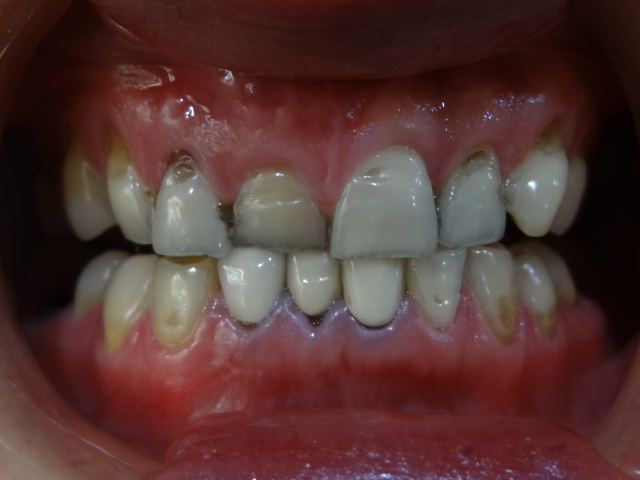

術(shù)前